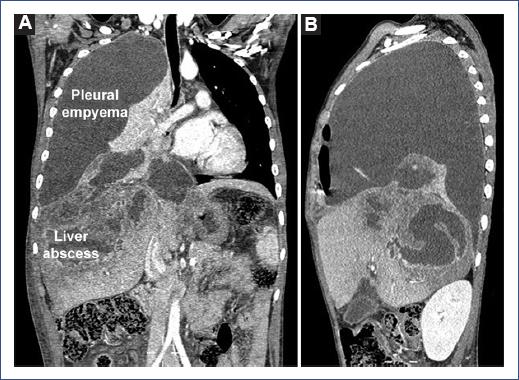

The patient received ceftriaxone 100 mg/kg/day and clindamycin 60 mg/kg/day for suspected common organisms. When the serology results for E. histolytica were received 5 days later, intravenous metronidazole 50 mg/kg/day was added. Ceftriaxone, clindamycin, and metronidazole were administered for 28 days. The patient showed symptomatic improvement 7 days after starting antibiotic therapy and chest tube placement (which remained for 21 days); fever peaks persisted until day 10 of hospitalization, and he had a hospital stay of 42 days. Clinical evolution at 2 months follow-up was favorable, with the resolution of the hepatic abscesses and some sub-segmental atelectasis of the right lower lobe (Figure 2).

Clinical improvement has been reported between 3 and 6 weeks of follow-up5,10,11. However, there are also reports of fatal cases due to multisystemic involvement and liver failure9,12. In our case, clinical improvement and absence of liver abscesses were observed after 2 months of follow-up.